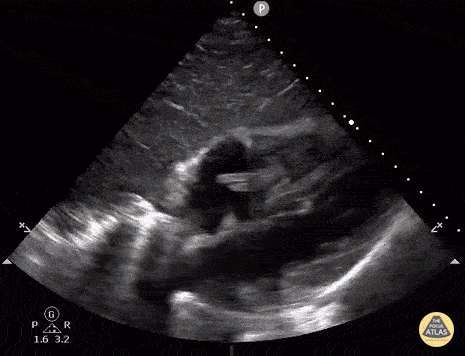

Subcostal view of a patient with a history of IV drug use. Ultimately this patient was diagnosed with a polymicrobial endocarditis of the tricuspid valve with MRSA and Candida Albicans as culprits. Note the hyperechoic lesion swinging between the right atrium and right ventricle. Image courtesy of Robert Jones DO, FACEP @RJonesSonoEM Director, Emergency Ultrasound; MetroHealth Medical Center; Professor, Case Western Reserve Medical School, Cleveland, OH View his original post here